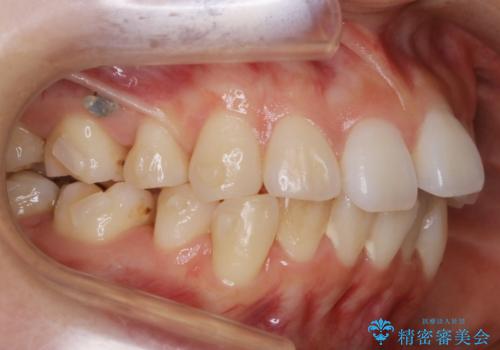

- 以前、中学生から高校生にかけてワイヤー装置による抜歯矯正を経験されている患者さんで、大人になってからのライフスタイルの変化でリテーナーを継続使用することができず、ガタつきが目立つようになってきてしまったのでもう一度矯正治療がしたいという主訴でご来院されました。

既に上下左右の4番目の歯が抜歯されているため、今回の治療では抜歯をせず歯の移動だけでガタつきを治す必要があり難易度が高くなっていました。

小学生~高校生の頃に一度矯正治療を経験している方も、その後の生活の変化の中でリテーナー(後戻り防止装置)の継続使用が困難となり、時間の経過とともにガタつきが再発現してしまうケースが多くあります。

最初の治療の時点で抜歯をしている場合や、ガタつきの度合いによっては再治療といえど初回の矯正治療と同じくらいの期間を要する場合もあります。